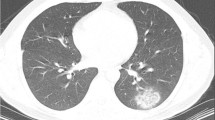

Considering results expressed in liters, significant differences were reported for GGOs (0.55 ± 0.26 L vs 0.43 ± 0.23 L, p = 0.0005) and fibrotic alterations (0.05 ± 0.03 L vs 0.04 ± 0.03 L, p < 0.0001) (Fig. 2). No significant differences were found for total lung volume (4.09 ± 1.49 L vs 4.20 ± 1.28 L, p = 0.37), healthy parenchyma (3.36 ± 1.58 L vs 3.64 ± 1.33 L, p = 0.11) and consolidations (0.06 ± 0.04 L vs 0.06 ± 0.03 L, p = 0.31). No significant differences were found in the evaluations of lung parenchyma expressed in percentage. Full results are shown in Table 2.

57-year-old man with COVID-19 (a, b) and 58-year-old man non-COVID-19 (c, d). Axial unenhanced quantified Chest CT scans that show diffuse bilateral ground-glass opacities (GGOs) and some fibrotic alterations in COVID-19 patient (a, b) and rare ground-glass opacities in non-COVID-19 patient (c, d). Chest CT semi-automatic quantification shows GGOs in red, vessels in yellow and fibrotic alterations in blue, these findings are more represented in COVID-19 patient (a) then in non-COVID-19 patient (c)